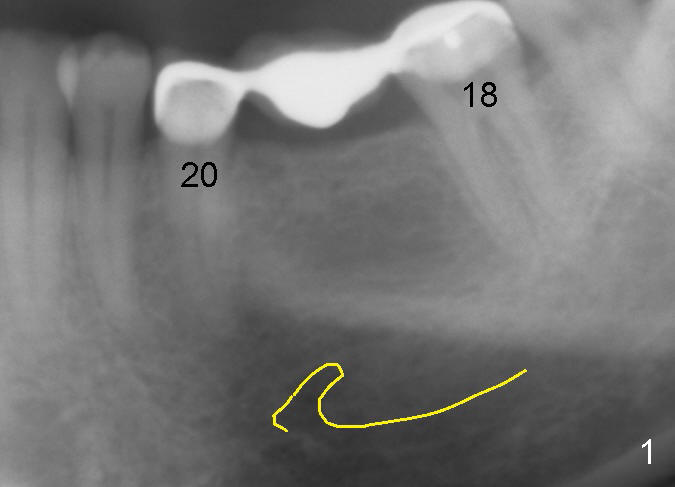

A 47-year-old man has lost a lower left fixed partial denture (FPD) for a while (Fig.1,2). There is limited space between the abutments (of the teeth #18 and 20) and the opposing dentition. The edentulous ridge is wide enough to use a 4 mm tissue punch. A 5.3x14 mm bone-level implant is to be placed (Fig.2). The base of the implant is at the level of the apices of the neighboring teeth. As compared to Fig.1 in term of the Inferior Alveolar Canal (yellow line), there should be enough safe margin. The first intraop PA is taken after 2 mm pilot drill for depth and trajectory check, Drill stops are to be used for safety. If primary stability is achieved, an abutment is placed and a provisional bridge will be fabricated to prevent further narrowing of the interocclusal clearance during 3-4 months of osteointegration. How is outcome?